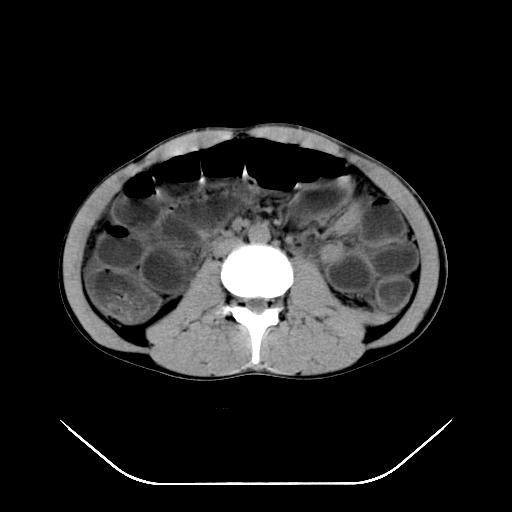

m-25y 高空堕落 12 月5号

12月7号病人尿量200ml/24h 急查双肾ct

左肾挫裂伤并肾周血肿;

左肾挫裂伤并肾周血肿

支持 : 左肾挫裂伤并肾周血肿

支持:1、左肾挫裂伤并肾周血肿;

2、少量腹水;

3、左肾旋转不良;

4、反射性肠淤张。